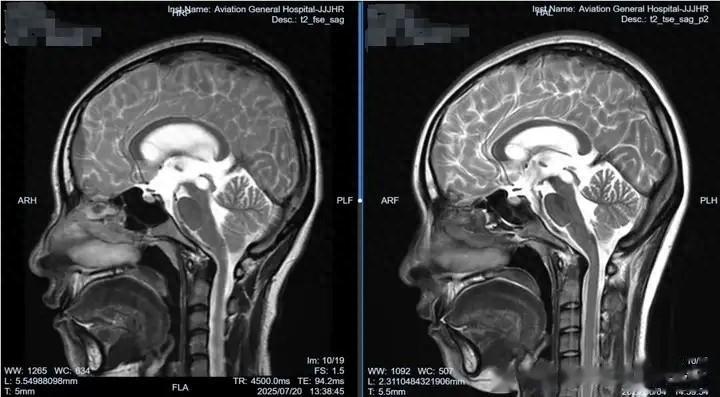

术前术后显著对比

术后妮娜的病症消失,复查影像学流空影证实疗效显著,脑脊液化验正常,避免了在体内植入永久性分流装置及可能面临的更多未知并发症。